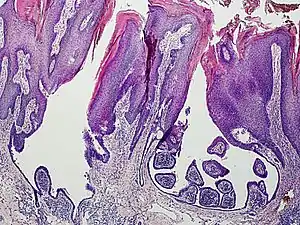

An example of a syringocystadenoma papilliferum